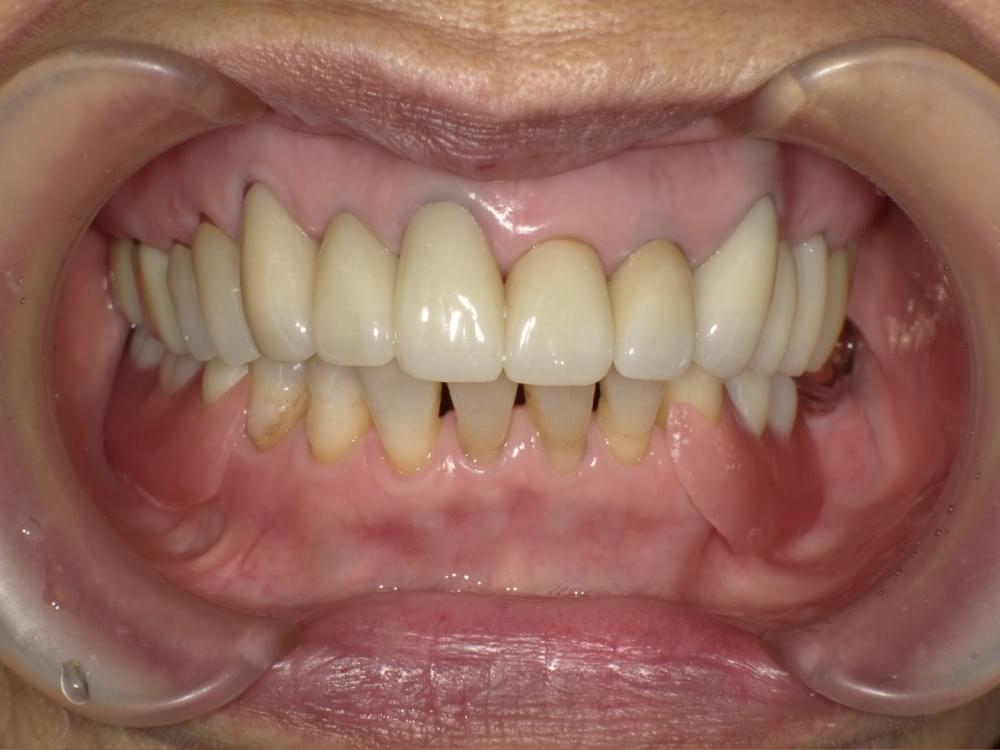

歯周病治療プログラムの治療例2

歯ぐきが下がってきた理由が分かりました!

歯ぐき下がりとかぶせ物の関係

治療の概要

治療内容

精密検査→歯周病治療プログラム→セラミック治療

※歯周病治療プログラムは行動科学に基づき、「自分の歯は自分で守る」という意識改革や行動変容を促しながら、スケーリングや歯ブラシ・フロス指導を行いました。

治療期間・回数・時間

6ヶ月・18回・計18時間

費用

精密検査 18,000円+税

歯周病治療プログラム 29,500円+税

セラミック治療(95,000円+税)×6本

リスク・副作用

歯肉の痛み・出血